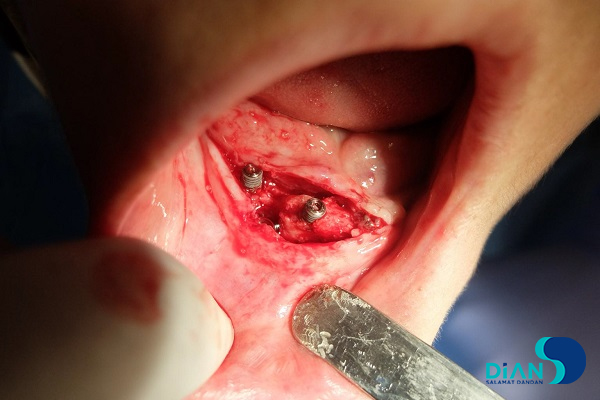

A patient with fully edentulous upper jaw and bridgework on the lower jaw came to dental clinic seeking for dentition restoration. After examination, the dentist decided to extract bridgework and to place implants from Bio3 in teeth sockets. After bridgework extraction, the dentists started to form implant beds. Then he placed implants from Bio3 Implants. Next stage was to place PRF-clot and bone tissue material into the wound and suture it. In first part of this clinical case we saw placement of dental rehabilitation using implants by Bio3. In this part you can find the result of first implantation with bone augmentation and additional placement of implants by Bio3. This case report was presented by Dr. Saniye Tümay (Turkey).